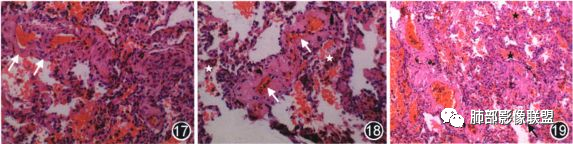

3.肺静脉闭塞病(PVOD)是一类罕见的动脉性肺动脉高压(PAH),其起病隐匿,病程进展迅速,靶向药物治疗效果差,预后不良。患者从起病到死亡或接受肺移植的平均病程仅22.4个月,患者无特异性临床症状,多数患者仅仅以乏力、运动 耐量下降、胸闷气短为主诉;随着疾病进展,逐渐出现如纳差、消瘦、浮肿等右心功能衰竭表现。病理学的肺组织标本病理显示不同直径的肺小静脉和肺静脉发生广泛性、弥漫性闭塞样病变;肺小静脉血管内膜增厚;肺泡腔内可见大量巨噬细胞沉积以及广泛出血。影像学方面,多数 PVOD 患者在肺部高分辨 CT可见到以下两项或以上影像学表现 (1)纵隔淋巴结肿大;(2)马赛克征;(3)小叶间隔增厚;(4)肺动脉高压;PVOD患者胸部高分辨CT常可见上述特征性表现,其中以马赛克征改变最为常见。